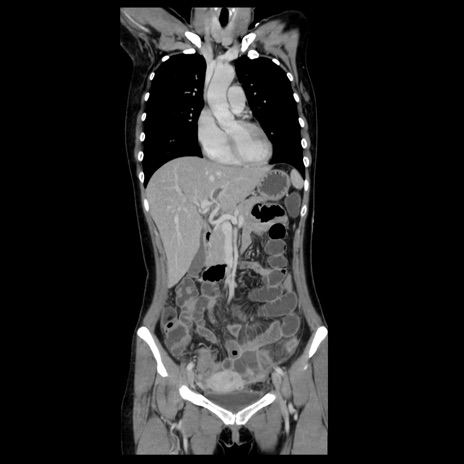

症例39(冠状断像)

【症例】40歳代女性

【主訴】上下腹部痛

【現病歴】2日目から下腹部痛あり。夜間は痛みで眠れなかった。昨日より上腹部痛と下痢が出現。臥位で痛みは軽快したため、休んでいた。本日になって臥位でも立位でも痛みが強くなってきたため救急要請。

【既往歴】子宮内膜症

【身体所見】部:平坦・軟、左上下腹部に圧痛あり、反跳痛あり。

【データ】WBC 21800、CRP 26.78

CT